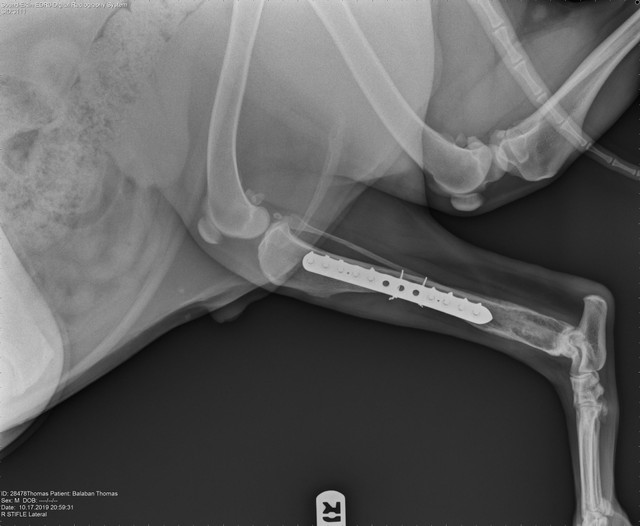

Наиболее распространенным способом лечения данной злокачественной опухоли является ампутация пораженной конечности с последующей химиотерапией. Иногда проводятся операции с сохранением конечности, если опухолью поражено не более 50% кости и она не распространилась на окружающие мышцы. При таком методе пораженная кость удаляется хирургическим путем и заменяется костным трансплантатом.

Протезированием лучевой кости у собаки после удаления саркомы.

| Рис. 4. Остеогенная саркома. | Рис. 5. После постановки имплантата. | Рис. 6. Замещение удаленного участка кости акриловым полимером с использованием пластины. | |